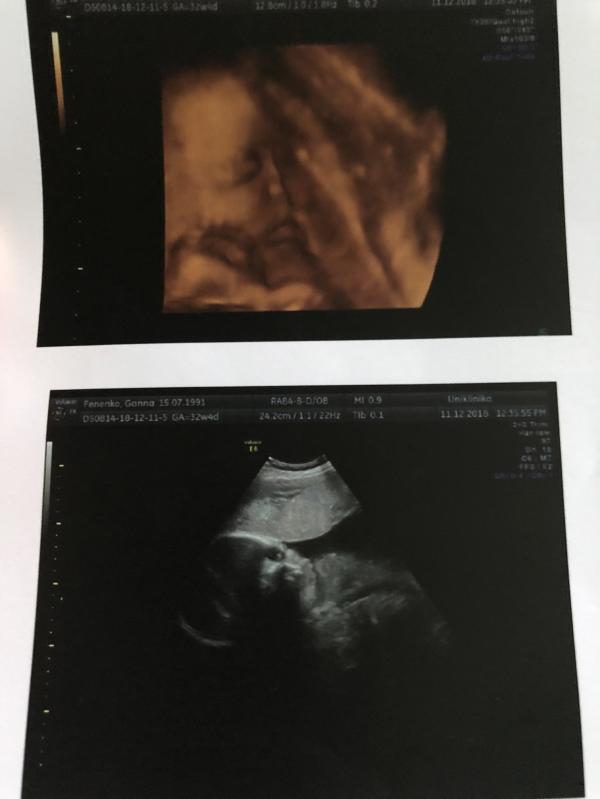

11.12)) долгожданное узи))) малыш очень активный, крутился-вертелся))) но пару фоток удалось всё-таки сделать))))

Все у нас по срокам))) 32недельки и 4 дня))) срок на 1е февраля)))

Наш вес 2кг189гр❤️

Наше щекастое чудо)))))😍